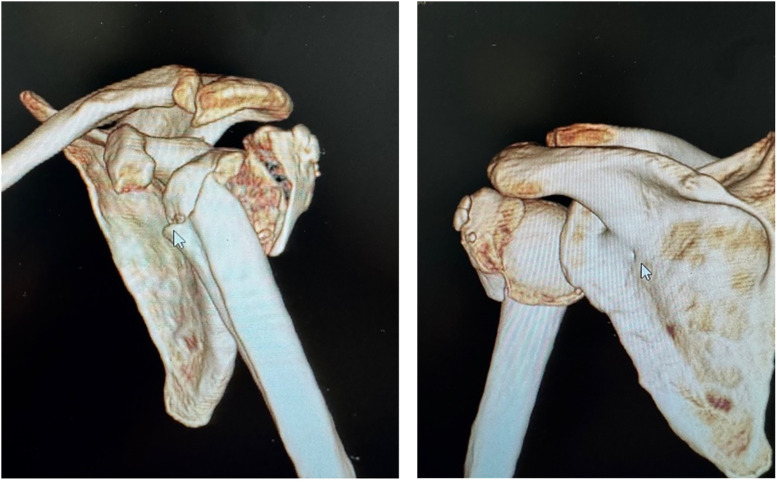

Conclusion: In the elderly population, reverse shoulder arthroplasty utilizing a fracture-specific locking stem, low-profile metaphysis, suture-friendly groove, meticulous suture technique, and local bone grafting allows adequate fixation, variable prosthesis height adjustment, and enhances greater tuberosity healing. This approach yields positive short-term clinical outcomes without complications related to the stem's locking screws.

Abstract Image